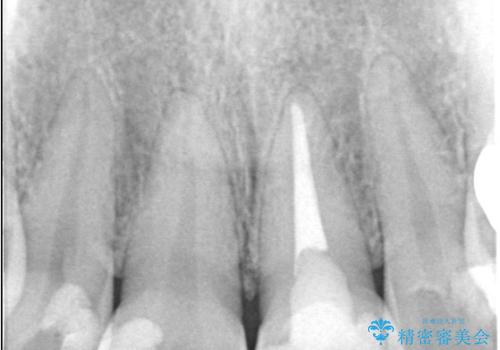

- 「前歯の色が気になる」を主訴に来院された患者様です。

前歯にプラスチックの材料が入っており、形と色が悪くなっていました。

失活歯だったため全体的に歯の色が暗くなっていました。

右上1もCRが入っており治療を勧めましたが、希望されず左上1のみ行いました。